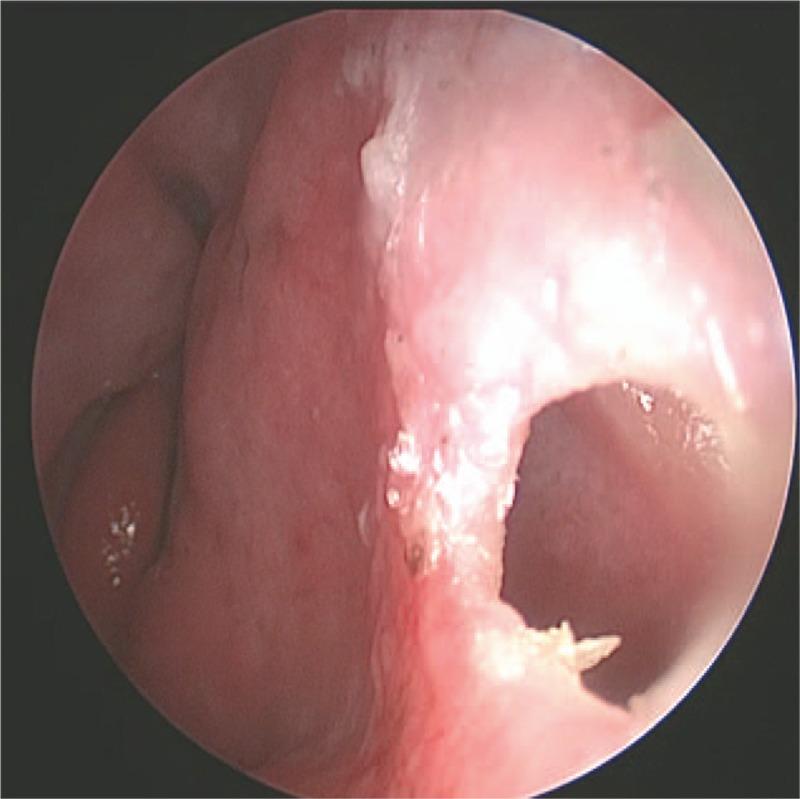

Spontaneous cerebrospinal fluid rhinorrhea is often treated by surgery, and a transsphenoidal approach repair is the main surgical method used, offering the advantages of less trauma, fewer complications, rapid postoperative recovery, and low recurrence rate.

自发性脑脊液鼻漏通常采用手术治疗,经蝶窦入路修补是主要的手术方法,具有创伤小、并发症少、术后恢复快、复发率低等优点。